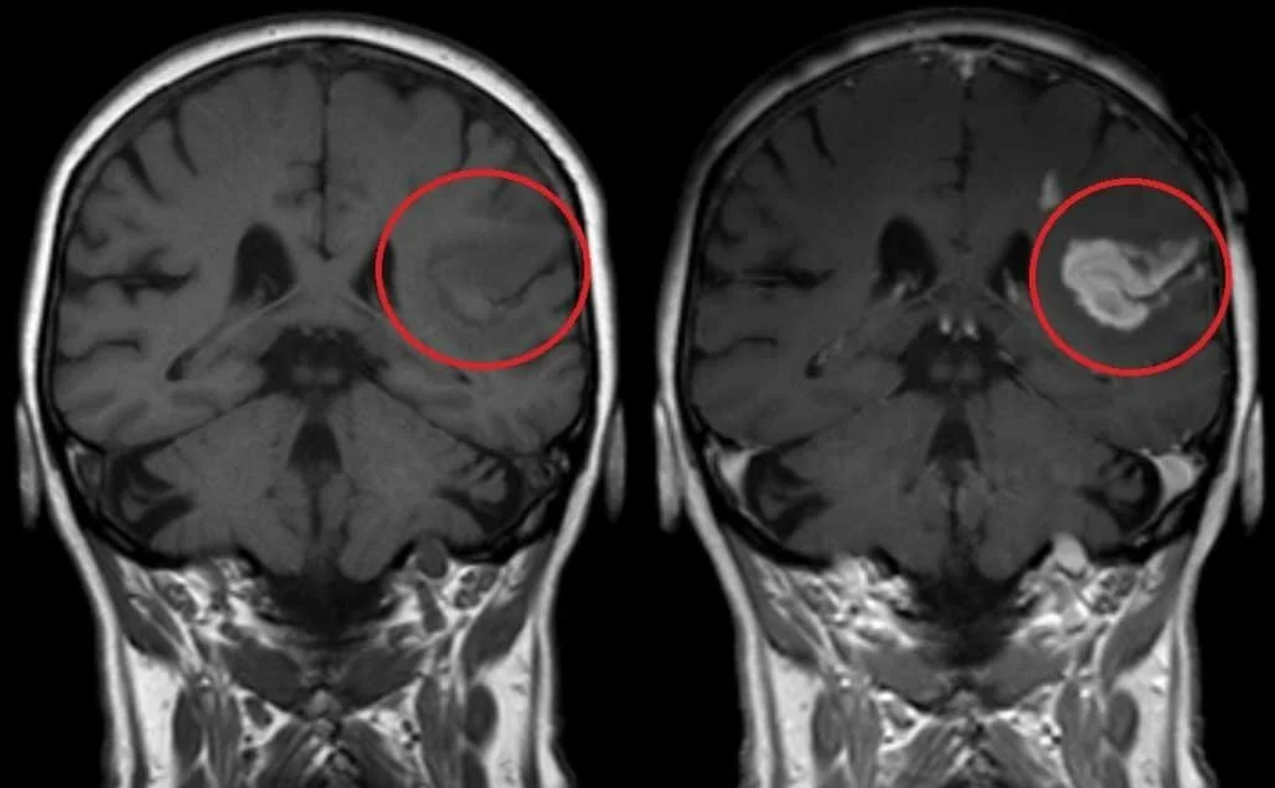

Медицинская диагностика: КТ и МРТ головного мозга